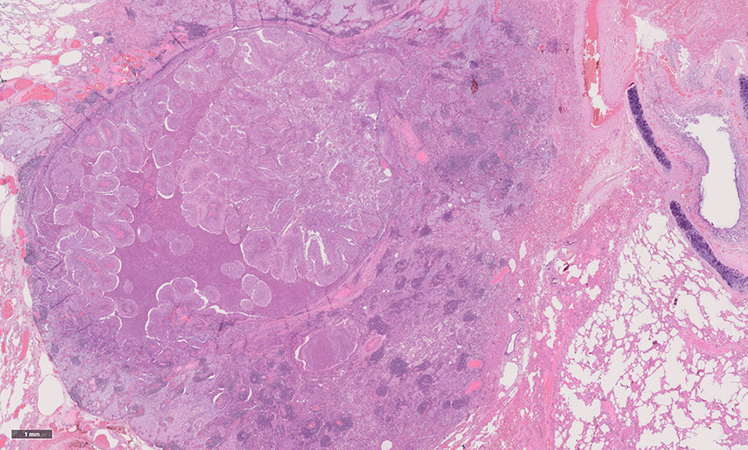

Clinical History: A PET-positive 1.5-cm solitary central pulmonary nodule was resected in a 67 year-old woman (non-smoker). The clinical suspicion was malignancy. Macroscopically, the nodule was tan-white and well demarcated. As depicted in Figure 1 (H&E) and Figure 2 (EvG), histologically the nodule was predominantly endobronchial with minimal alveolar extension and consisted of a papillary tumor. There was an acute inflammatory infiltrate between the fibrovascular cores. The surrounding lung parenchyma showed mucostasis and lympho-follicular inflammation, which could be attributed to a post-obstructive complication. The fibrovascular cores were lined by glandular epithelium with pseudostratified ciliated and non-ciliated cuboidal to columnar mucin-filled cells (Figure 3) and interspersed areas of acanthotic squamous epithelium (Figure 4, H&E; Figure 5, p40). There was no atypia, karyorrhexis or necrosis.